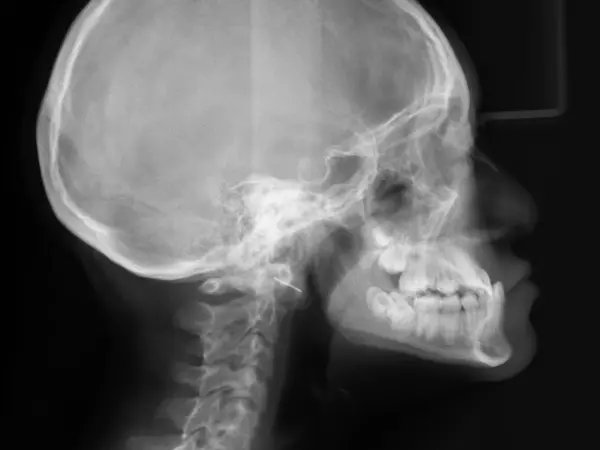

A crossbite is a type of malocclusion created when the upper and lower jaws are misaligned, causing improper overlap of the top and bottom rows of teeth. If left untreated for too long, the patient may eventually need surgery, which can be expensive and complex.

To correct crossbites with Invisalign treatment, your orthodontist uses an iTero digital scanner to create a comprehensive image of your mouth, teeth, and roots, to effectively diagnose your condition and develop a treatment plan. The carefully developed regimen of aligners will slowly draw your teeth into their correct positions. In certain cases, a combination of braces and Invisalign treatment may be necessary to achieve the best results, or the doctor may refer you for oral surgery to surgically remove or adjust certain teeth.